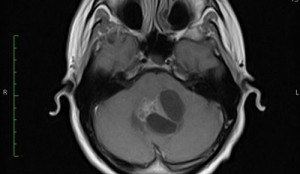

Ez nem nehéz meghatározni a tomográfiás vizsgálatok a tumor az agyban. A diagnózis fibrillaris astrocytoma csak akkor lehetséges eltávolítása után, és azt mikroszkóppal megvizsgálják. Minden más módszereit és attribútumok lehetővé teszi számunkra, hogy megítélje a természet a daganat csak közvetve.